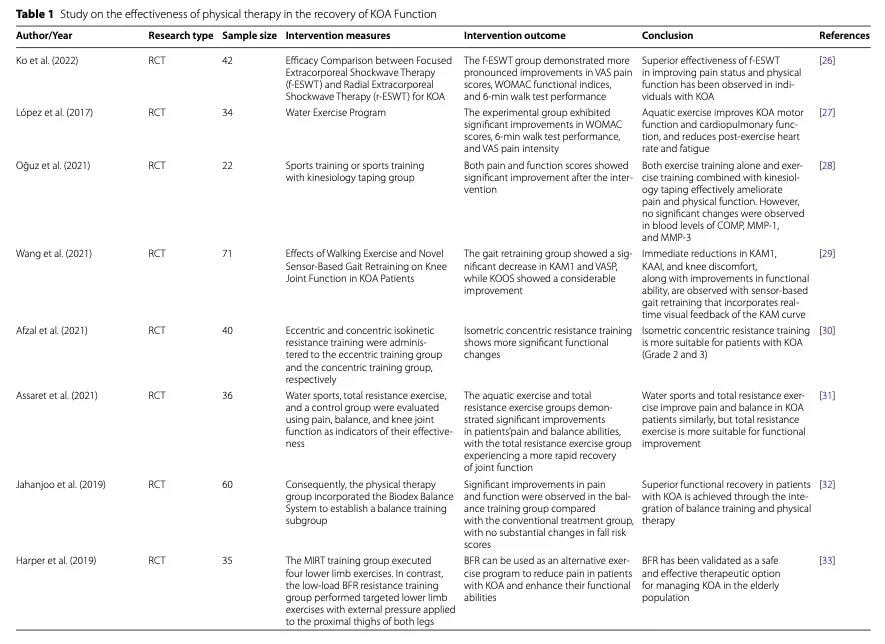

结果

风险因素和保守治疗

膝关节骨关节炎的风险因素众多,包括生物力学因素、缺乏运动、肥胖、肢体排列异常以及先前的关节损伤或创伤。 保守治疗 膝关节骨关节炎康复的保守疗法 应旨在减轻这些可改变的风险因素。 除治疗性运动外,一些学者还提出了支具、矫形鞋垫、活动度辅助工具和特定物理治疗方法(如超声波、体外冲击波疗法、脉冲电磁场和低强度激光疗法)等干预措施,作为潜在的相关辅助手段,但其效果参差不齐,应被视为运动康复的辅助手段。

饮食干预

体重管理在 膝关节骨关节炎康复中发挥着核心作用。. 研究表明,减轻 5-10% 的体重可明显减轻疼痛并改善功能。 减肥还与全身炎症标志物的减少有关,包括肿瘤坏死因子-α(TNF-α)、白细胞介素-6(IL-6)和C反应蛋白(CRP),这些标志物与软骨降解有关。

除了限制热量外,还应考虑营养质量。 富含欧米伽-3 脂肪酸的膳食通过调节炎症通路表现出消炎特性,有助于减轻疼痛和改善功能。 富含纤维的膳食通常来自水果和蔬菜,与降低全身炎症有关,还能提供维他命 C 和 E 等抗氧化剂,从而降低氧化压力和炎症活性。

生物力学方法

膝关节负荷分布的改变会增加关节软骨的机制压力,导致症状进展。 因此,旨在优化下肢对齐和减少关节过度负荷的干预措施可改善疼痛和功能。 值得注意的是,已发现步态期间膝关节内收力矩增加与疼痛严重程度、疾病进展和内侧间室退化之间存在关联。

矫形器,包括鞋垫、膝关节支具和行走辅助器,可减少膝关节受到的机制约束。 侧面楔形鞋垫可通过侧面转移地面反作用力来减少膝关节内收力矩,可能特别适用于膝关节屈曲和内侧骨关节炎患者。 然而,目前支持将鞋垫用于 膝关节骨关节炎康复的证据仍然无力且不一致,这可能是由于患者表现和生物力学反应的异质性。

步态再训练

步态再训练策略旨在减少膝关节内收力矩,而膝关节内收力矩与膝关节内侧骨关节炎的严重程度和进展有关。 以生物反馈为基础的干预措施(如鞋内压力传感器)已显示出改变步态机制的有效性,而使用镜子进行视觉反馈则可能提供一种低成本的替代方法。

包括躯干倾斜、膝关节内侧推力("内侧推")、缩短步长和趾外翻步态在内的特异性策略已被证明可通过改变下肢对齐和负荷模式来减少膝关节内收力矩。 然而,这些策略可能会增加相邻关节(髋关节或踝关节)的负荷或增加肌肉的共收缩,从而可能会增加压迫力和症状。

物理治疗师干预

物理治疗师在采用生物心理社会方法治疗膝关节骨关节炎方面发挥着核心作用。 全面的评估应包括对关节力学、运动范围、肌肉力量、本体感觉和步态的评估,并辅以临床病史和经过验证的结果测量,如 WOMAC 和 SF-36。